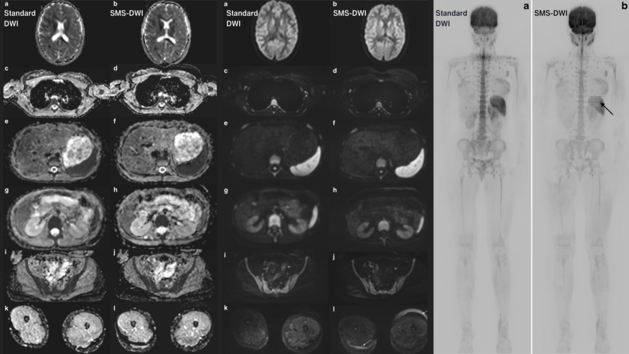

Strukturierte Befundung und Künstliche Intelligenz in der Prostatadiagnostik: Prof. Dr. Thorsten Persigehl im Interview

Wie sieht Radiologie aus, wenn strukturierte Befundung und Künstliche Intelligenz aufeinandertreffen? Ein Blick in die Praxis von Prof. Dr. Thorsten…